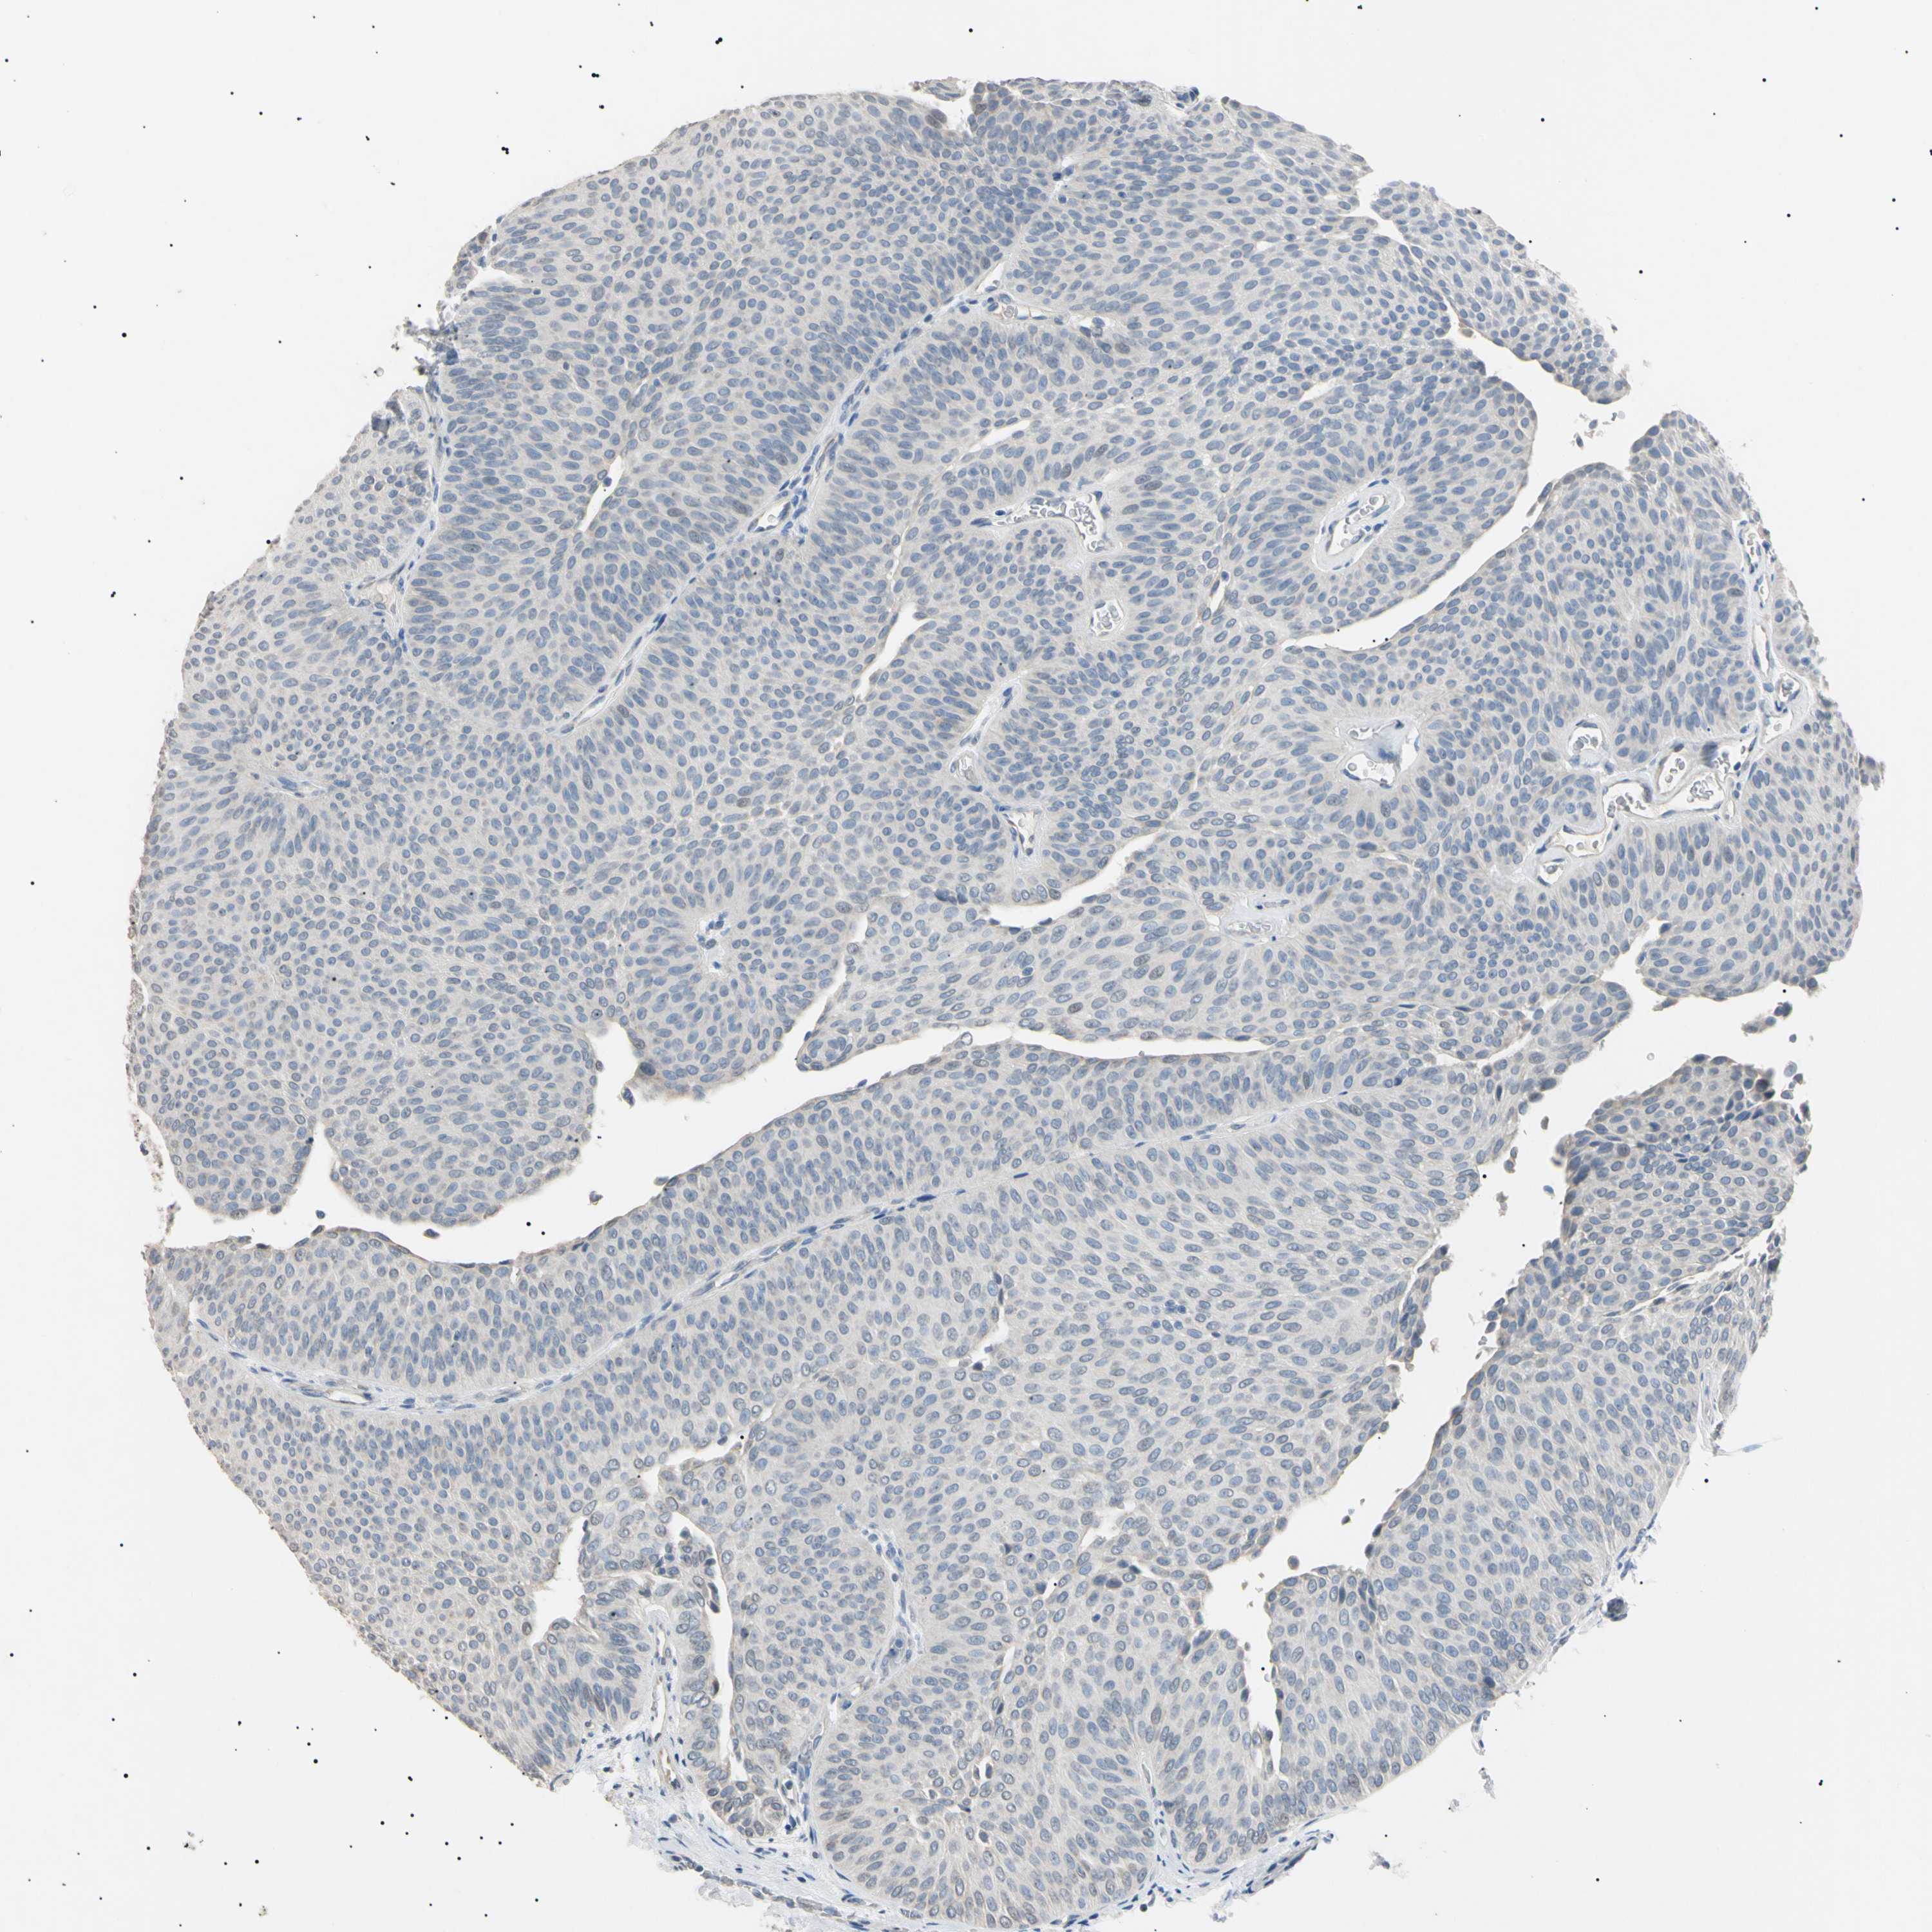

UROTHELIAL CANCER - Protein expressioni

A mouse-over function shows sample information and annotation data. Click on an image to view it in a full screen mode. Samples can be filtered based on level of antibody staining by selecting one or several of the following categories: high, medium, low and not detected. The assay and annotation is described here.

Note that samples used for immunohistochemistry by the Human Protein Atlas do not correspond to samples in the TCGA dataset.

Antibody stainingi

Antibody staining in the annotated cell types in the current human tissue is reported as not detected, low, medium, or high, based on conventional immunohistochemistry profiling in selected tissues. This score is based on the combination of the staining intensity and fraction of stained cells.

Each image is clickable and will lead to virtual microscopy that enables deeper exploration of all samples and also displays staining intensity scores, fraction scores and subcellular localization as well as patient and tissue information for each sample.

Antibody HPA038925

Antibody HPA038934

Antibody CAB000042

Antibody CAB010884

Staining

High

Medium

Low

Not detected

Intensity

Strong

Moderate

Weak

Negative

Quantity

>75%

75%-25%

<25%

None

Location

Nuclear

Cytoplasmic/membranous

Cytoplasmic/membranous,nuclear

Urothelial carcinoma, High grade

Urothelial carcinoma, Low grade

Adenocarcinoma, NOS